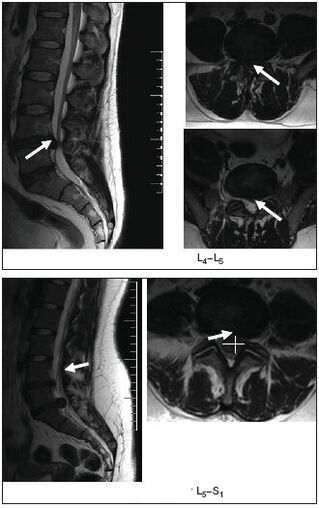

MRI

Magnetic resonance imaging A highly accurate diagnostic method that helps visualize the smallest changes.It will help establish a diagnosis both at an early stage and in complex cases before surgical treatment.